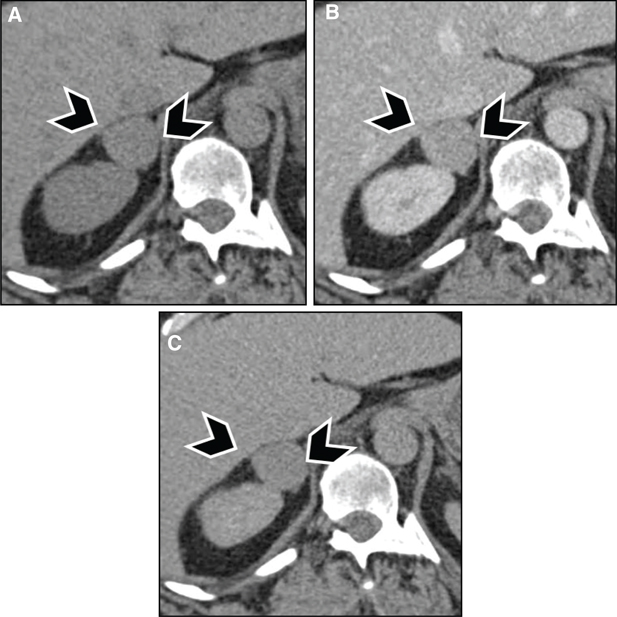

Fig 3

Figure 3 Pheochromocytoma in a 39-year-old male patient with neurofibromatosis type 1. (A) Noncontrast images demonstrate a hypodense lesion in the right adrenal gland (arrowheads), with (B) marked enhancement after contrast administration. (C) Adrenal washout phase acquired 15 min after contrast administration demonstrates rapid washout, which is usually seen with adrenal adenomas but can be seen in one-third of pheochromocytomas. The patient had elevated metanephrines, and surgical pathology was consistent with pheochromocytoma.